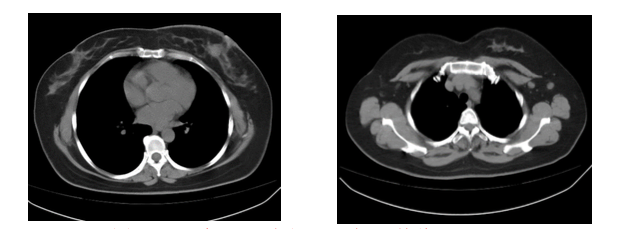

2.胸部CT平扫(图1):两肺小结节,部分淡薄;左肺舌段纤维灶;左乳占位伴皮肤增厚。双侧腋下淋巴结显示,右侧腋下一肿大淋巴结。左乳可见数个结节影,较大者位于左乳头后方,大小约21.7 mm × 17.4 mm,伴左乳晕周围皮肤增厚。双侧腋下淋巴结显示,右侧腋下一肿大淋巴结,短径约13.6 mm。

图1 2018年5月 胸部CT平扫(基线)